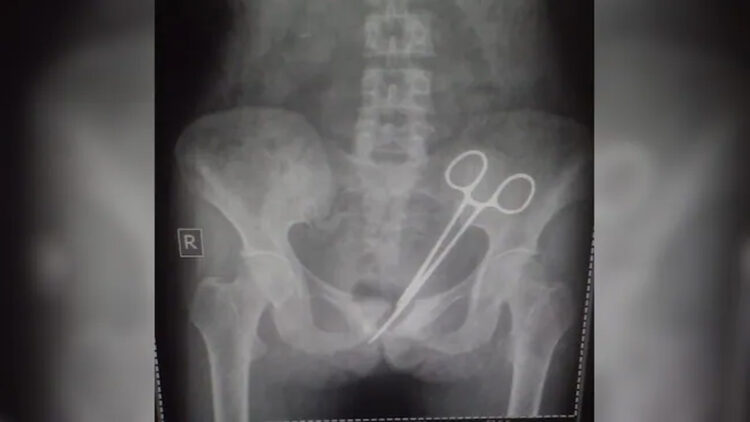

45 കാരിയുടെ ശരീരത്തിൽ നിന്നും 12 വർഷം മുമ്പ് മറന്നുവെച്ച കത്രിക നീക്കം ചെയ്തു. സീക്കിമിന്റെ തലസ്ഥാനമായ ഗാംഗ്ടോക്കിലാണ് സംഭവം നടന്നത്. കടുത്ത വയറുവേദനയെ തുടർന്ന് നടത്തിയ എക്സറേ പരിശോധനയിലാണ് ശസ്ത്രക്രിയ ഉപകരണം കണ്ടെത്തിയത്.

ഒടുവിൽ ഒക്ടോബർ 8 ന്, യുവതി ഭർത്താവും വീണ്ടും മുൻപ് അപ്പെൻഡിക്സ് ശസ്ത്രക്രിയ നടത്തിയ ആശുപത്രിയിൽ എത്തി. സീനിയർ ഡോക്ടർമാരുടെ നിർദ്ദേശപ്രകാരം നടത്തിയ വിശദ പരിശോധനയിലാണ് കത്രിക കണ്ടെത്തിയത്. ഉടൻ തന്നെ കത്രിക പുറത്തെടുക്കാനുള്ള ശാസ്ത്രക്രിയ നടത്തുകയും ചെയ്തു. വാർത്ത പുറത്ത് വന്നതോടെ ആശുപത്രിക്കെതിരെ അന്വേഷണത്തിന് സർക്കാർ ഉത്തരവിട്ടു.